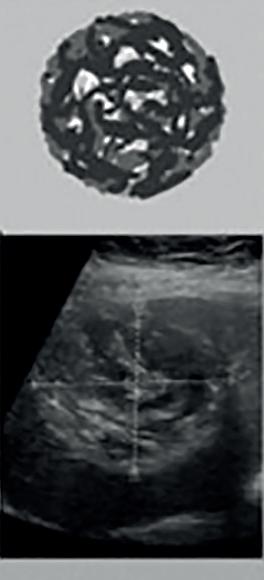

Magdalena Stefaniak, Monika Derda Bąblowica jednojamowa (echinokokoza) – epidemiologia, zwalczanie i profilaktyka zarażenia